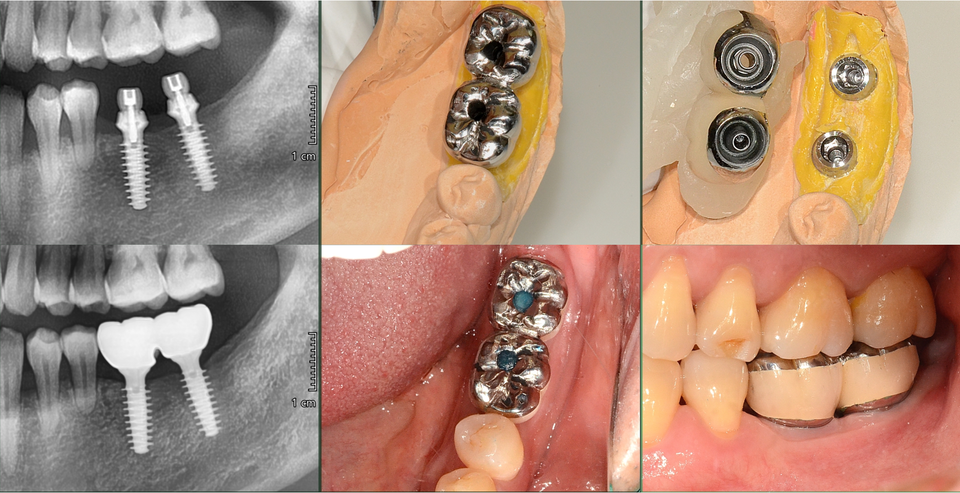

#36,37술전/후CT를통해 2년여의 장기간무치악 상태로 disuse atrophy로 의심되는 수질골(medullary bone)의 골질저하를 보였다 (그림5,6).

이것을 개선하고 빠른bone healing을 위해 MagiCore식립즉시 인상채득하여 교합되지 않는 비기능 임시치아로 splinting함으로써 저작, 연하 등의 정상기능 활동 시, 혀 와 협근의 압박에 의한 physiologic stimulation을 활용하고자 했다(그림7).

식립 2개월 후 abutment와 통상적인 Cr.이 하나로 결합되어 있는 Magic Cr.으로 최 종 보철하였다(그림8).

Ferrule (external connection)과dowel (internal connection)이 모두 금속으로 double connection 되어 있는 Magicconnection의 MagicCr.은 필자가 가장 선호하는 보철방 식이며 장기간의 사용시 cervicalchipping을 예방하기 위해 metalmargin을 두껍게 제 작한다.

술전에 장기간의 무치악으로 위축되어 있던 #36, 37협측치은은 최소한의 절개와 연조직에 손상을 주지 않는 Magic Drill의 특성으로 gingivalexpansion 하였다.

수술 후 점착된 결합조직과 접합상피를 인상채득과 보철체결과정 동안 전혀 분리시키지 않고 유지하는 Magic Cuff 의 장점으로 확장된 치은조직이 유지되고 개선되는 것을 확인할 수 있다(그림 9).